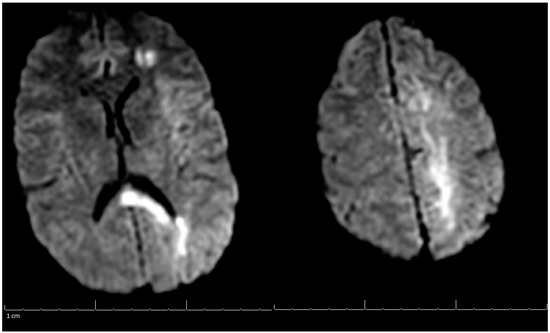

On her outpatient neurology clinic follow-up six weeks later, the patient was doing very well and largely back to her baseline. She still endorsed mild headaches about every other day and was using acetaminophen (Tylenol) for pain relief. The patient had been progressing well from attending regular physical therapy, occupational therapy, and speech therapy. Due to no seizure-like events, Keppra was to be weaned off to 500 mg every two weeks. Decreased Tylenol use was also suggested to avoid a rebound phenomenon. She was medically cleared to return to work and driving. Her three-month post-hospitalization MRV of the head showed stable left occipital intraparenchymal hemorrhage concerns for venous hemorrhage; partial thrombosis of the left transverse sinus improved in appearance compared with the previous examination three months ago; unremarkable appearance to the superior sagittal sinus, internal cerebral veins, inferior sagittal sinus, right transverse sinus, right and left sigmoid sinuses and internal jugular veins (Figure 3). A lipid panel showed improvement from inpatient levels. At the following telemedicine visit five months later, the patient reported only residual right hand weakness associated with reduced hand grip, but no further headaches. She discontinued Keppra at her last visit and has tolerated it well. Based on her most recent MRV, lipid panel, and clinical improvement, Xarelto and Lipitor were discontinued. The patient was advised to continue to follow a healthy diet and exercise to keep cholesterol under control, and avoid estrogen-containing birth control. There are no limitations on her activities from a neurological perspective. Another follow-up was scheduled in six months to ensure there are no new concerns, however, the patient did not show for this visit.

Figure 3. MRV of the Head on 3-Months Post-Hospitalization.